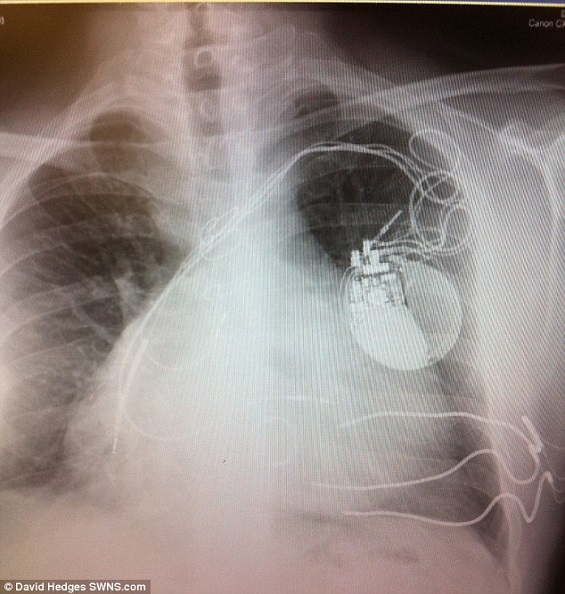

وكان الأطباء قد توقعوا وفاة كيفين ماشفورد (38 عاماً) بعد أسابيع قليلة وهو يصارع مرض القلب، ولم يدرك رجل الأعمال مدى خطورة حالته، إلا عندما أصيب بفشل في الكليتين والكبد وقصور في القلب، وكان لا بد من إجراء عملية زرع قلب لإنقاذ حياته.